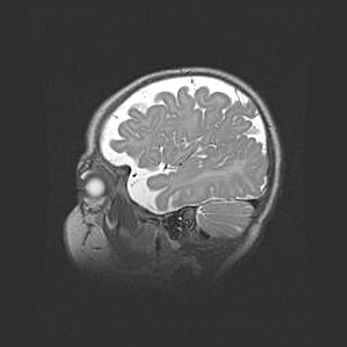

Мальформация Денди-Уокера. Киста задней черепной ямки.

Агенезия мозолистого тела.

Возраст: 2,5 месяца

Вес: 2420 г

Пол: женский

Окружность головы: 37 см

Срок гестации: 32 недели

Мальформация Денди—Уокера — редкий вид патологии ЦНС, представляющий собой врожденный порок развития каудального отдела ствола и червя мозжечка, ведущий к неполному раскрытию срединной (Мажанди) и латеральных (Лушка) апертур IV желудочка мозга. Для этогно синдрома характерна триада симптомов: гипотрофия червя мозжечка и/или полушарий мозжечка, кисты задней черепной ямки, гидроцефалия различной степени. В 70% случаев порок сочетается и с другими аномалиями головного мозга, в частности с агенезией мозолистого тела.